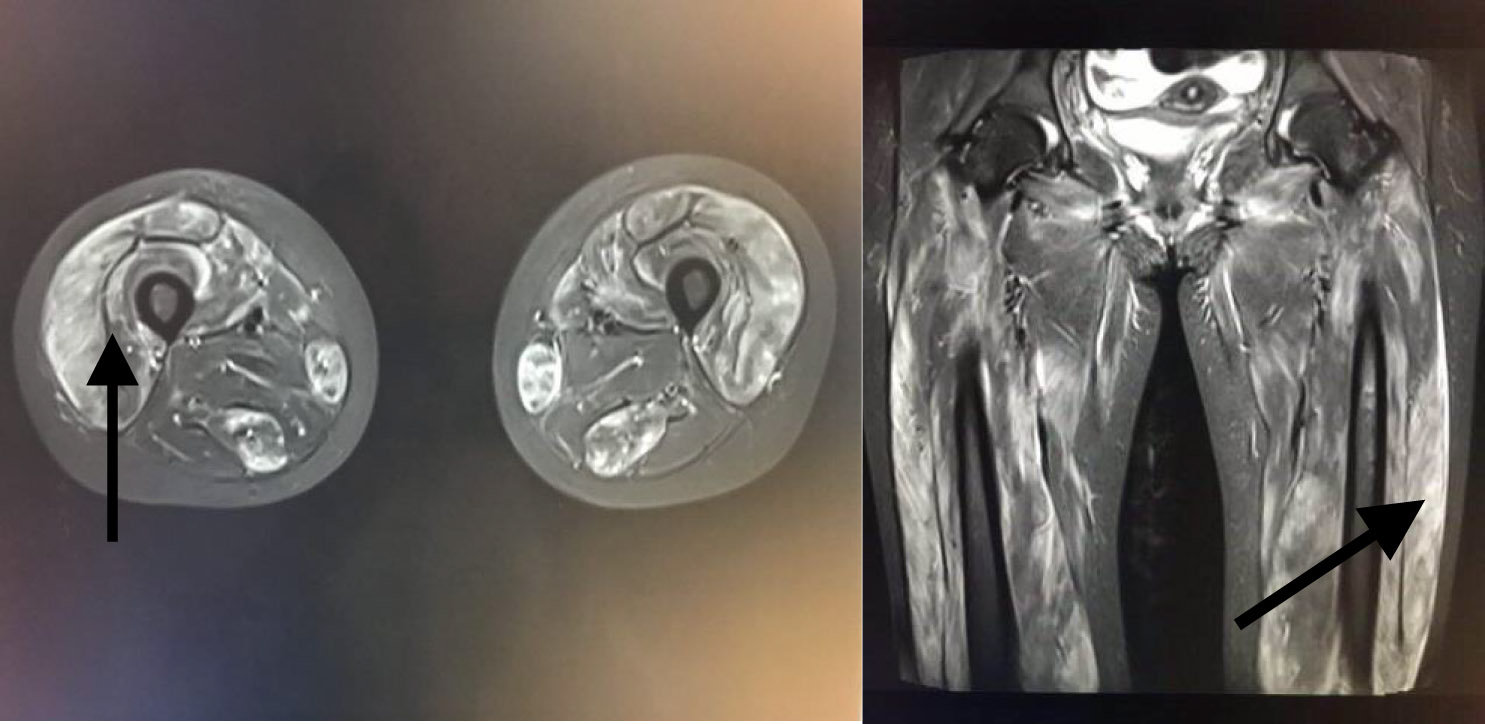

患者,女,20岁,主因“四肢无力9 d,无尿7 d”入院。9 d前无明显诱因出现乏力肌痛,伴随酱油色尿、少尿,当地医院查CK、尿肌红蛋白明显升高,予水化、碱化及透析治疗CK未见明显下降转诊。既往体健,否认用药史。查体:T37.8℃,P120次/min,RR18次/min, Bp147/68 mmHg(1mmHg=0.133Kpa), 双侧大腿可见瘀斑,轻度水肿,有压痛,近端肌力4级。双肺呼吸音低,未及啰音,心律齐,腹软,无压痛。辅助检查:血生化ALT1 065 IU/L,AST3 530 IU/L Scr332.7 μmol/L, eGFR16.375 mL/(min·1.73m2), BUN15.27 μmol/L, CK>8 000 U/L,肌红蛋白>4 140 ng/mL。尿常规:蛋白质+++,红细胞150~180 /HP,WBC100~120/HP。直接抗人球蛋白实验阴性。肌炎抗体阴性。血尿免疫固定电泳未见单克隆免疫球蛋白区带。感染方面筛查:肝炎抗体、CMV/EBV-DNA、呼吸道九种病毒、布氏杆菌、莱姆病、流行性出血热抗体、军团菌皆阴性;高通量病原体检测未检出原核微生物、病毒、真核微生物。重金属筛查阴性。糖化蛋白、甲状腺功能正常。肾脏超声:双肾体积增大且实质回声增强,结构欠清晰。大腿肌肉核磁:双大腿肌肉及双侧下肢肌带肌弥漫水肿,左侧股外侧肌肌筋膜水肿(图 1)。入院诊断横纹肌溶解合并急性肾损伤。治疗上,最初间断多次行高通量血液透治疗,血肌酐下降但尿量无明显恢复,且CK水平高居不下。进一步完善的肌肉活检结果(左肱二头肌肌肉)提示:肌纤维坏死、再生,伴随肌束血管周围少量炎细胞浸润,许多肌间毛细血管NSE深染,符合坏死性肌病样病理改变特点(图 2)。根据肌肉活检结果考虑免疫介导性坏死性肌病,行激素治疗(甲泼尼龙40 mg/d静点连续10 d后调整为口服泼尼松50 mg口服, 静脉激素治疗第3天时曾行甲泼尼龙500 mg静脉冲击1次)及2次血浆置换(每次分别置换3 000 mL)后CK明显下降,尿量也逐渐增多(图 3~4)。出院时患者口服强的松45 mg/d,尿量恢复至3 500 mL/d,生化结果:ALT67 U/L,AST26 U/L,Scr99.4 μmol/L, CK78U/L, 肌红蛋白23.5 ng/mL,尿肌红蛋白4.6 ng/mL。患者出院1个月后门诊复诊,血肌酐和ck正常,尿量正常,转归良好。

| 图 1 下肢MRI(箭头所指为肌肉水肿表现) |

NAM患者肌酶升高以CK为主,一般高于正常值10倍以上,发病初期可达数万。可同时伴有ALT、AST、LDH升高,一些NAM患者血清中肌炎抗体如抗SRP抗体、抗HMGCR抗体、肌炎特异性抗体(myositis specific autoantibody,MSA)可阳性表达。在MRI上,MNM可表现为STIR序列高信号,这提示组织水肿,臀大肌和股四头肌后方肌群受累易见。肌肉病理上,HE染色中,NAM的显著特点是大量肌纤维坏死,可见再生肌纤维。免疫组织化学染色可见肌纤维膜MAC和MHC-I阳性。本例患者为年轻女性,急性起病,双下肢近端肌痛、力弱,CK升高10倍以上,伴随肝酶升高,肌炎抗体阴性,肌肉核磁显示肌肉水肿,肌肉病理提示免疫介导的坏死性肌病,符合上述NAM诊断标准。糖皮质激素是治疗NAM的一线药物,对于病情严重或者初始治疗不佳患者,可给予静注激素。激素效果不佳可应用免疫抑制剂或者静脉应用丙种球蛋白。本例患者确诊NAM后,给予激素和丙种球蛋白治疗,血浆置换辅助治疗后CK、肝酶很快明显下降至正常,临床改善,转归良好。临床上,对经充分水化、特别肾脏替代治疗后CK仍高居不下的横纹肌溶解需考虑有炎性肌肉病可能。可区分MNM患者与横纹肌溶解患者的特征包括:症状和表现(包括CK升高)在不进行免疫抑制治疗时持续存在,进一步完善肌肉影像学检查和肌肉活检明确患者的组织病理学变化。尽早明确诊断、给予免疫调节治疗,可免漏诊误诊、减少患者痛苦。